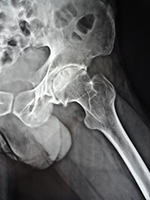

SNSA - CASE 1

1yr ap